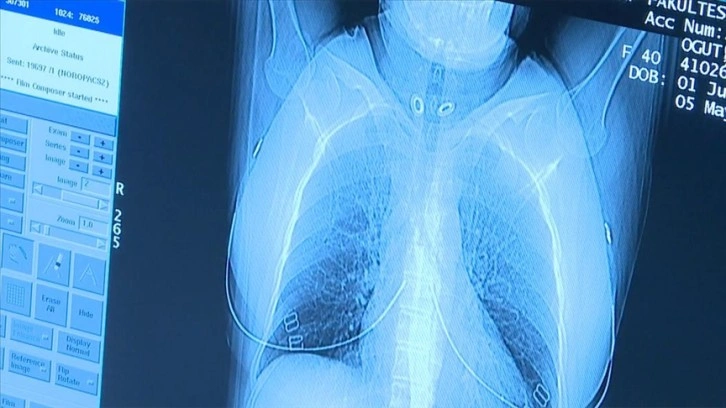

"Akciğer kanserinde erken tanı ve doğru evreleme ile radyolojik görüntüleme yöntemleri hasta yönetiminde önemli rol oynamaktadır. Akciğer kanserinde erken teşhis yüzde 77 oranında hayat kurtarmaktadır. 50 yaş üzeri ve 20 yıl ve daha uzun süreli sigara içen kişilerde yıllık düşük doz akciğer tomografisi çekilmesi önerilmektedir. Bu sayede, erken dönemde kanser tespiti yapılabilmekte ve tedavisi planlanabilmektedir. Ancak öncelikle kişinin yüksek risk grubunda olup olmadığı hekimi tarafından belirlenmeli ve gerek duyulduğu takdirde tarama yapılmalıdır.

İleri evre akciğer kanserinde tam tedavi oranı büyük oranda mümkün değilken, erken dönemde teşhis ve tedaviyle başarılı sonuçlar alınabilmektedir. Bu nedenle, risk grubundaki kişiler için belirlenen sürelerde düşük doz akciğer tomografisi hayati önem taşımaktadır."